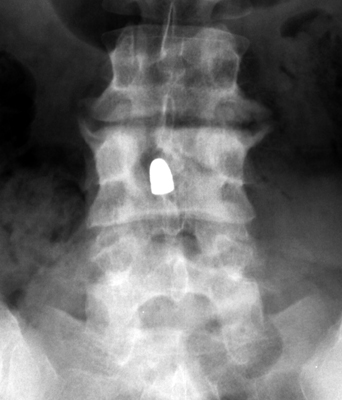

Tumbling Bullet Sign

Post traumatic bone cyst

Two sets of frontal and lateral radiographs, separated only by time, which reveal the "tumbling bullet sign"--which is simply a bullet which changes its location and orientation within a solitary bone cyst. This sign serves two purposes. It is documentation of the evolution of a solitary bone cyst as a corollary of trauma, and reveals the free movement of the foreign body within the confines of the lesion establishing its cystic rather than solid nature. It is similar to the fallen fragment sign.

- Click on the image for a larger versionA - Click on the image for a larger versionB - Click on the image for a larger versionC - Click on the image for a larger versionD

bulletTaxin RN, Feldman R.: The tumbling bullet sign in a post-traumatic bone cyst. Am J Roentgenol Radium Ther Nucl Med 1975 Jan;123(1):140-3.          [See related articles]